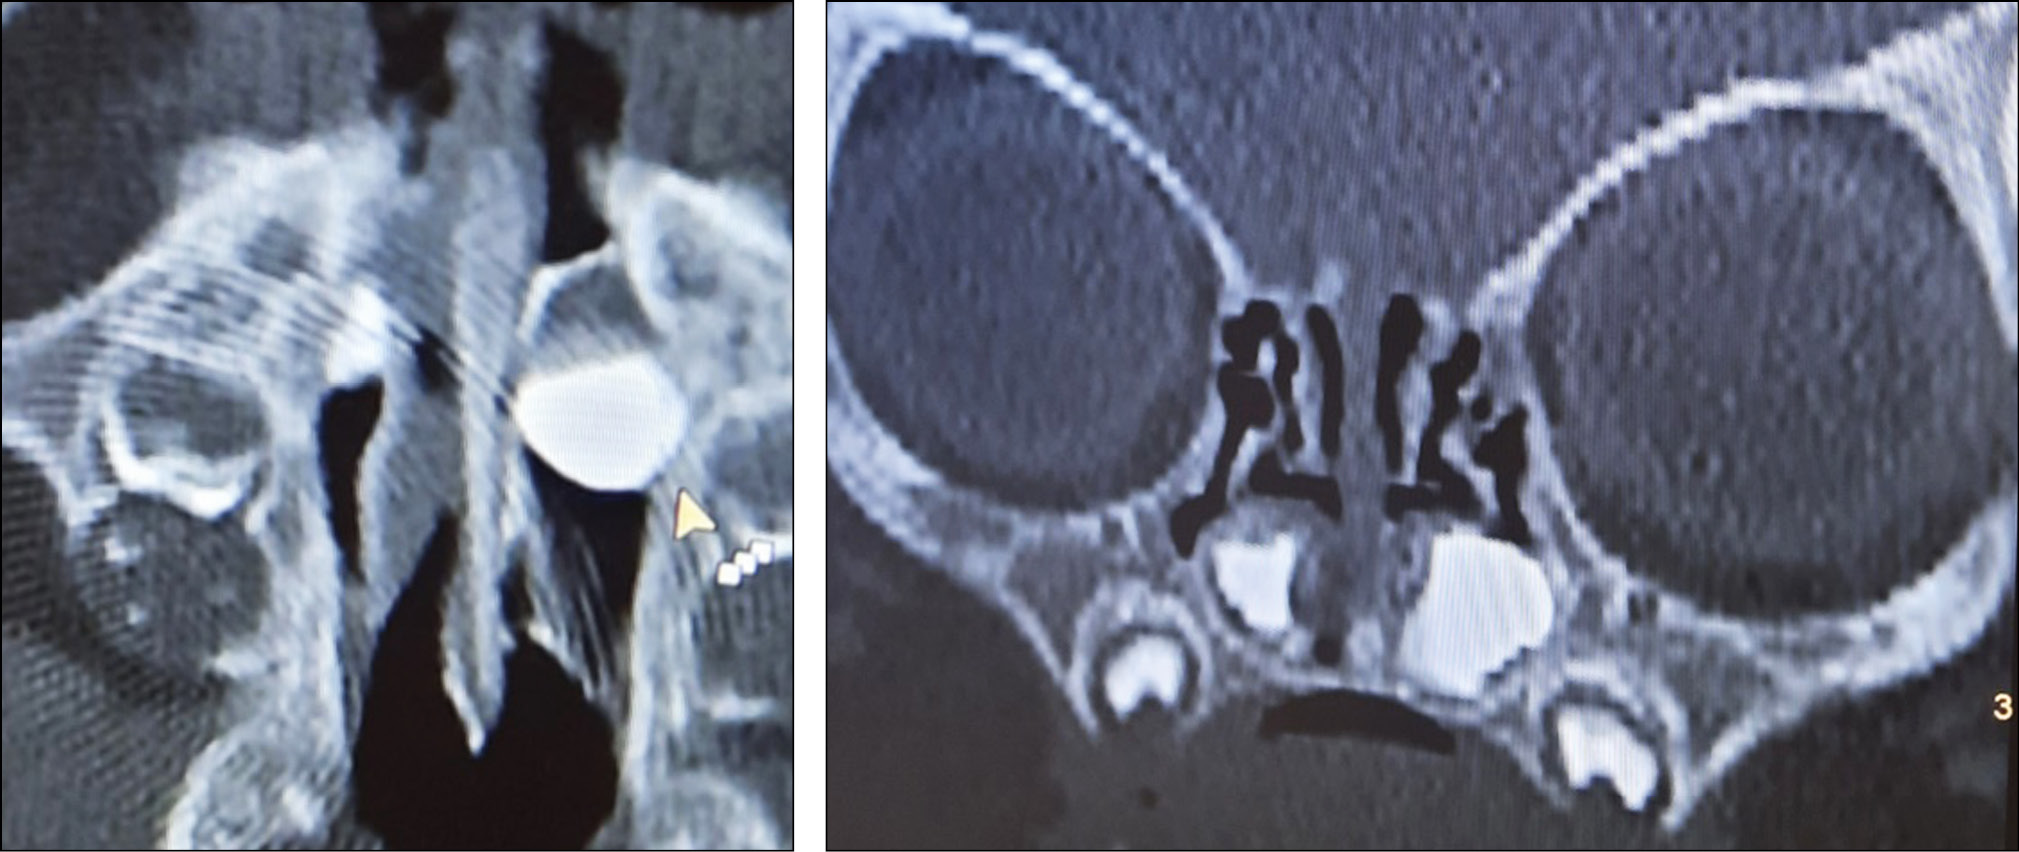

В возрасте двух месяцев ребёнок госпитализирован в офтальмологическое отделение клиники Университета. Проведена мультиспиральная компьютерная томография (МСКТ) слёзоотводящих путей с контрастированием (ультравист), по результатам которой обнаружены полостные образования под нижней носовой раковиной с обеих сторон с уровнем контраста (рис. 7). Слева визуализировалась полость значительно большего размера. Контраст в полости носа не прослеживался.

Рис. 7. Двусторонние назолакримальные кисты со скопившимся в них контрастом. / Fig. 7. Bilateral nasolacrimal cysts with accumulated contrast.